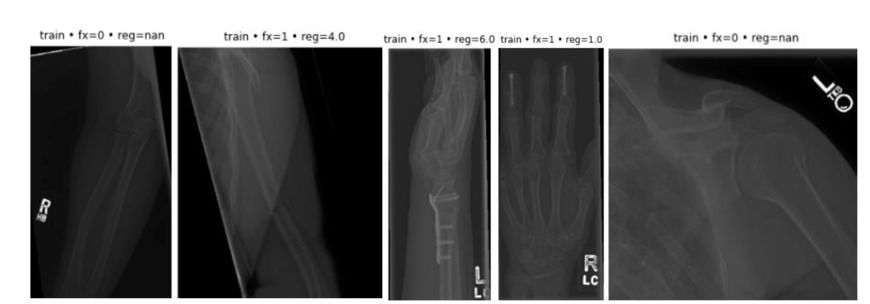

Figure 2: Sample images of bone region and fracture

Each image in the BoneFractureYolo8 dataset is annotated with bounding boxes or pixel-level segmentation masks that precisely delineate the location, size, and extent of bone fractures. These detailed annotations provide the essential ground truth required for training and evaluating deep learning models, enabling them to learn both spatial and contextual relationships between anatomical structures and fracture patterns. By integrating region-level and pixel-level supervision, the dataset facilitates the development of models capable of achieving high accuracy in automated fracture localization and detection.

To illustrate the dataset’s structure and variability, Table 1 presents representative radiographs along with their corresponding fracture status and anatomical regions. Specifically:

• Image 1 depicts a humerus and shoulder radiograph with no fracture.

• Image 2 shows a humerus and shoulder radiograph with a fracture.

• Image 3 illustrates a forearm fracture.

• Image 4 presents an elbow radiograph without fracture.